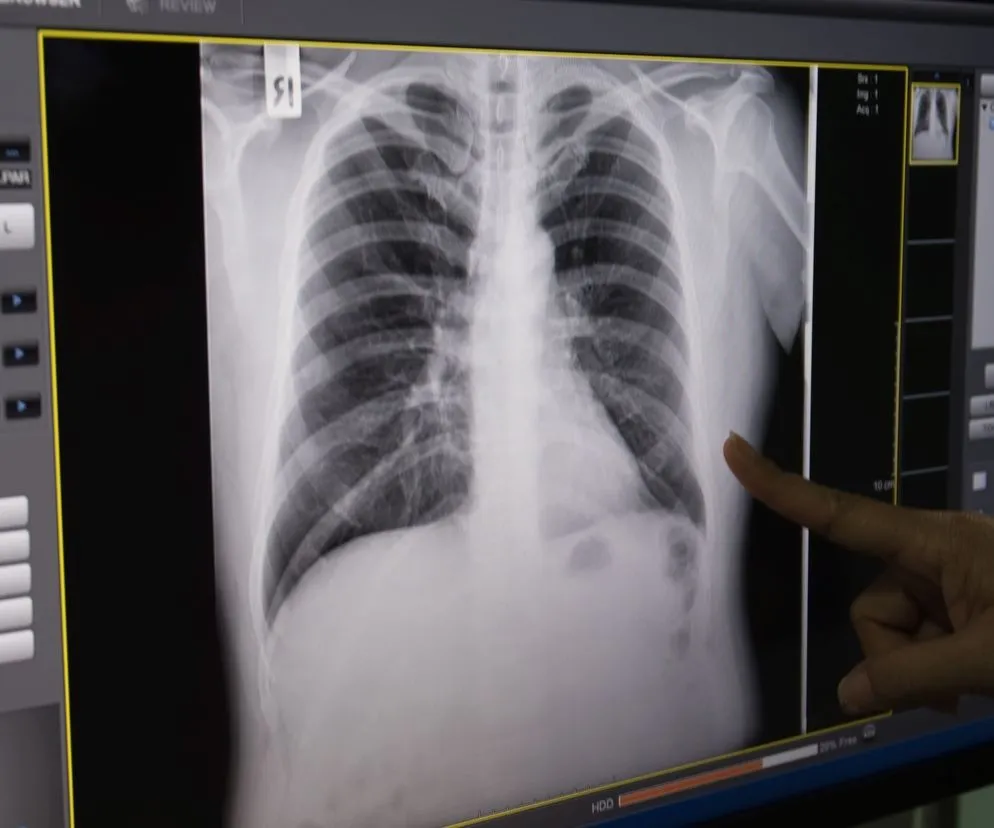

Po udzieleniu pierwszej pomocy kluczowe jest jak najszybsze skonsultowanie się z lekarzem. Diagnostyka złamania żeber zazwyczaj rozpoczyna się od RTG klatki piersiowej, które pozwala uwidocznić miejsce urazu i ocenić jego charakter. W bardziej skomplikowanych przypadkach, gdy istnieje podejrzenie uszkodzenia narządów wewnętrznych lub gdy RTG nie daje jednoznacznych wyników, lekarz może zlecić dodatkowe badania, takie jak tomografia komputerowa (TK) lub ultrasonografia (USG). Na podstawie wyników badań i stanu pacjenta lekarz decyduje o dalszym postępowaniu czy leczenie będzie odbywać się w domu, czy też konieczna jest hospitalizacja.

- RTG klatki piersiowej